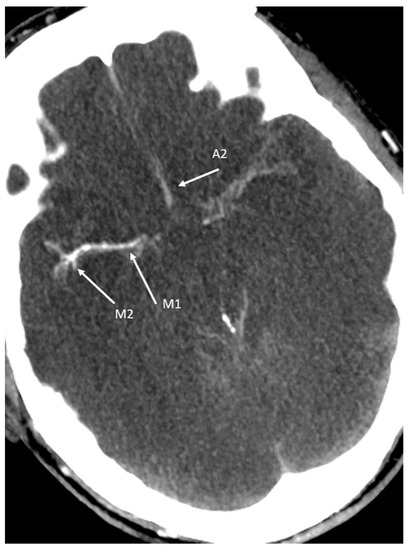

- Compared to DSA, Zampakis et al. [44] found no statistically significant difference between all CTA -4-point scores and in general, the 4-point CTA scoring system has been accepted as the most reliable scoring among other CTA scoring systems in the diagnosis of BD. However, some challenges still exist [46]. For completeness, it should be noted that there are different versions of the 4-point score [44]: the 4-point scale introduced by Frampas et al. [38] (the so-called CTA-F (by this score only the M4 branches of the middle cerebral artery and the internal cerebral vein are assessed);

- The revised 4-point scale suggested by Nunes and co-workers [47] (the so-called CTA-MF) and

- The prior revised venous 4-point scale, proposed by Marchand and colleagues [48] (the so-called CTA-M).

| 10-point scoring | MCA-M4: (2) | ACA-A3: (2) | PCA-P2: (2) | BA: (1) | ICV: (2) | GCV: (1) | (-) | 10 |

| 7-point scoring | MCA-M4: (2) | ACA-A3: (2) | (-) | (-) | ICV: (2) | GCV: (1) | (-) | 7 |

| 4-point scoring (CTA-F) | MCA-M4: (2) | (-) | (-) | (-) | ICV: (2) | (-) | (-) | 4 |

| 4-point scoring (CTA-M) | (-) | (-) | (-) | (-) | (-) | GCV: (2) | SPV: (2) | 4 |

| 4-point scoring (CTA-MF) | MCA-M4: (2, a) | ICV: (2, b) | 4 | |||||